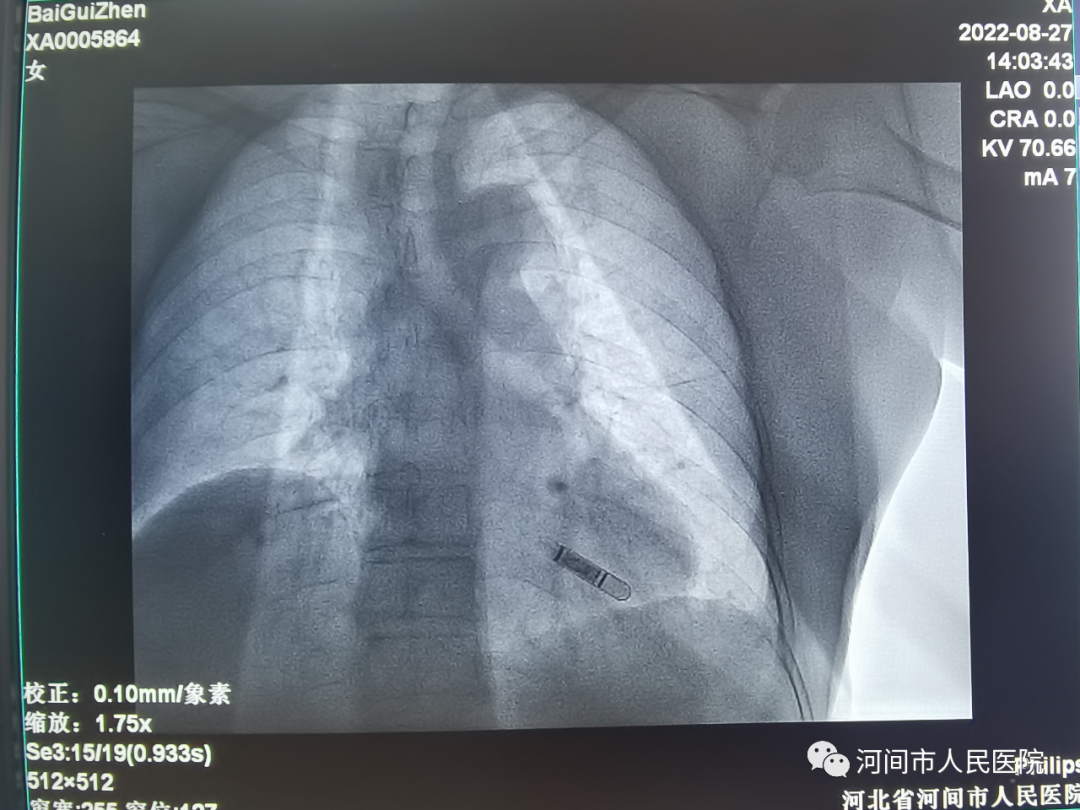

手术植入中

完善相关检查并排除手术禁忌后,在局麻下,于患者左胸切开约1厘米的切口,做好相应囊袋将心电记录器置入皮下后缝合,手术时间约15分钟。手术操作简单、创伤小,患者几乎感觉不到痛苦。